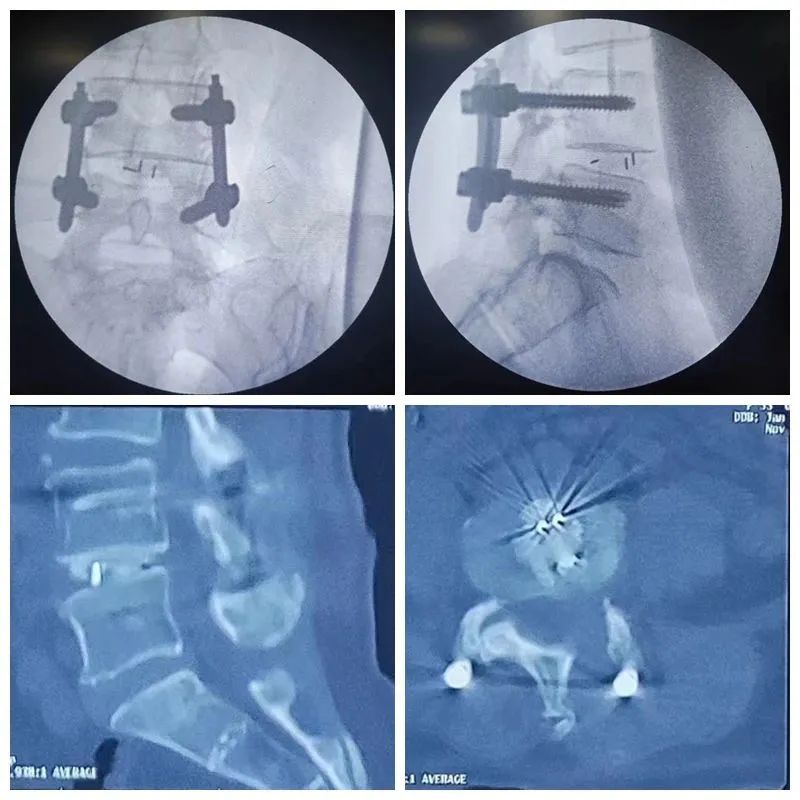

手术过程

术后复查显示腰4椎体滑脱完全复位,

内固定良好

术后第2天查房时,吴女士疼痛评分仅有1-2分,原来左下肢的麻木症状也消失了。术后复查X线片提示患者的腰椎滑脱完全复位,融合器位置良好。术后复查CT提示植骨量充足,椎间处理范围堪比开刀手术。术后5天患者即可轻松下地行走活动,解除困扰其多年病痛的同时也避免了开放手术的创伤和痛苦。术后1周患者顺利出院,可以自己坐起、行走活动、上厕所,已基本达到了生活自理。